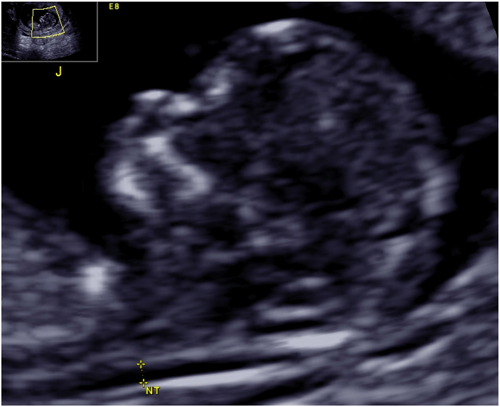

近年,胎児の染色体異常スクリーニングとしての系統だった超音波検査が普及してきた.Nuchal translucency(NT)(Fig. 1),鼻骨形成(NB)(Fig. 2),静脈管血流(DV),三尖弁血流(TR)などのいくつかのパラメーターを評価し,胎児の染色体異常をスクリーニングする方法である.特にNTは一見,計測しやすいと思われるため,その意義が十分に認識されることなく普及してしまった.確かにNTは21 trisomyのスクリーニング精度が比較的高い.母体年齢だけでのdetection rateが約30%であるところにNTの情報を加味するとdetection rateは約80%に上昇する.しかし,NTを正確に評価するためにはTable 2に示すような要件を満たさなくてはならない.また,NTにはいまだに多くの誤解があり,適切なカウンセリングがなされていない場合も少なくない.例えば,NTはどの胎児にも認められる生理的な所見である.特定の期間におけるその厚みが意味を持つにもかかわらず,NTが見えたことがあたかも異常な部位が見えたかのように説明されてしまう場合が後を絶たない.The Fetal Medicine Foundation(FMF)はNTを含めた全てのパラメーターに正確な測定が求めており,一定の要件を満たす計測以外,スクリーニングツールとして用いることはできない.

Fig. 1 Nuchal translucency

Nuchal translucency (NT) is the sonographic appearance of a collection of fluid under the skin behind the fetal neck.